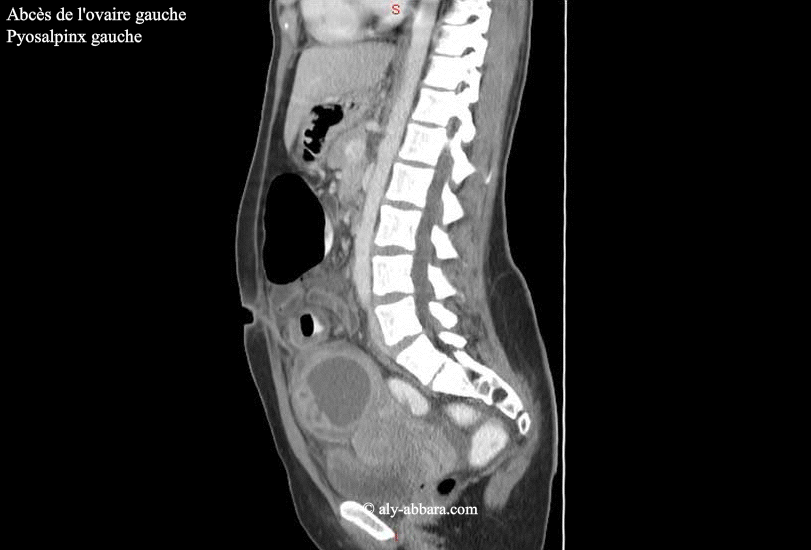

Salpingite Aigue Abces Ovarien Et Pyosalpinx Scanner